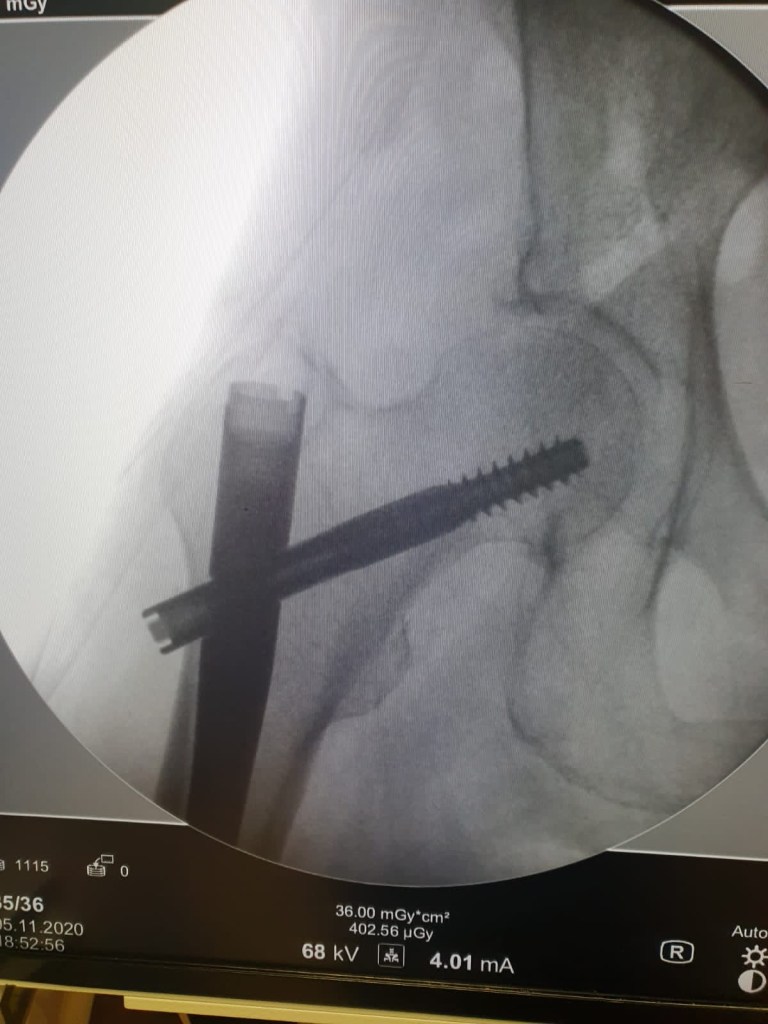

- Cheville

- Fractures